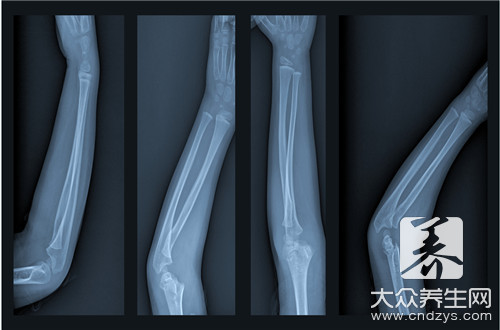

骨轉(zhuǎn)移疼痛的患者別到處問了,有辦法緩解。晚期骨轉(zhuǎn)移疼痛的患者,西醫(yī)一般用一些止痛藥,但效果都不太好,要搞清楚它為什么會疼痛。首先惡性腫瘤的產(chǎn)生,由于各種原因外感的內(nèi)傷的多...